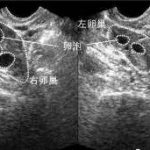

4、泰国试管婴儿促排取卵并不会使得女性卵巢早衰

试管进周之后,使用促排药物来促排卵,其实只不过是用药物将这些凋亡的卵泡催熟,相当于废卵利用,在使用合理的促排药物剂量的情况下是不会影响到卵巢功能,更不会使得卵巢早衰。但是为了更好保障试管的成功以及更安全可靠,广大患者朋友们一定要找正规知名专业的医院和有资质、临床经验丰富、试管技术精湛的医生进行试管手术。